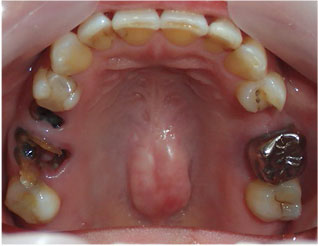

- ブリッジ 症例写真 B-0110オールセラミッククラウン4本 男性モニターの方です。

この方はご来院時には前歯や奥歯に欠損部分がありました。 当院では1回目の治療時に仮歯を入れますので、すぐに見た目が気にならなくなります。 上下の歯の治療を同時進行で治療しますので、通院回数は保険診療よりも少なく済みます。